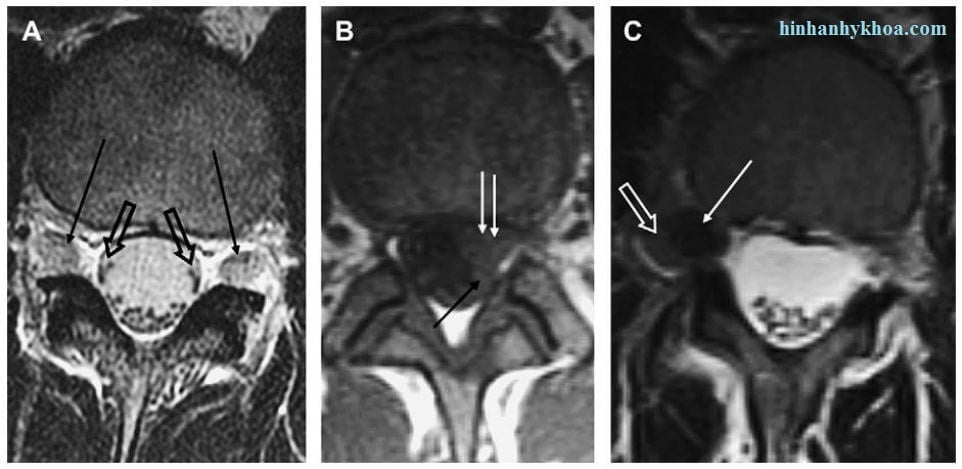

Hình 12. Hình axial T2W (A, C) và T1W (B) chỉ ra các dấu hiệu khác nhau. (A) các rễ thoát thần kinh bình thường (mũi tên đen) và các rễ thần kinh chạy ngang bình thường (mũi tên đen hở). (B) Protrusion dưuói mặt khớp và trung tâm trái (mũi tên trắng) đẩy lệch rễ thần kinh chạy ngang (mũi tên đen). (C) thoát vị đĩa đệm trong lỗ liên hợp đẩy lệch rễ thoát thần kinh (mũi tên trắng hở) về phía sau bên.